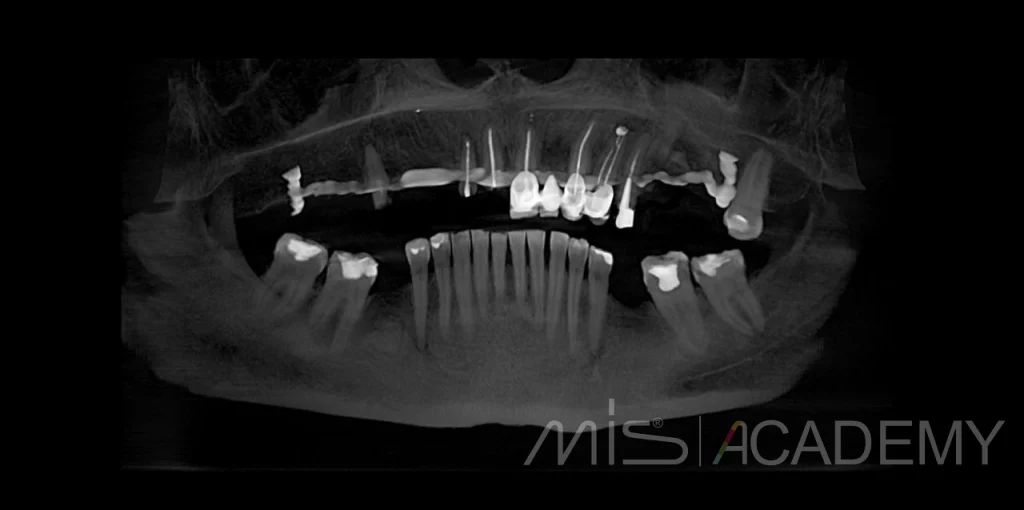

Реабилитации пациентки по протоколу, верхняя челюсть

1. Удаление 8 зубов.

2. Установка 4 имплантов MIS C1 + Multiunit.

3. В области 1.4 проведен B2S.

4. В областях 1.4, 1.2, 1.1, 2.1, 2.2, 2.4 проведена подсадка мягких тканей с бугра.